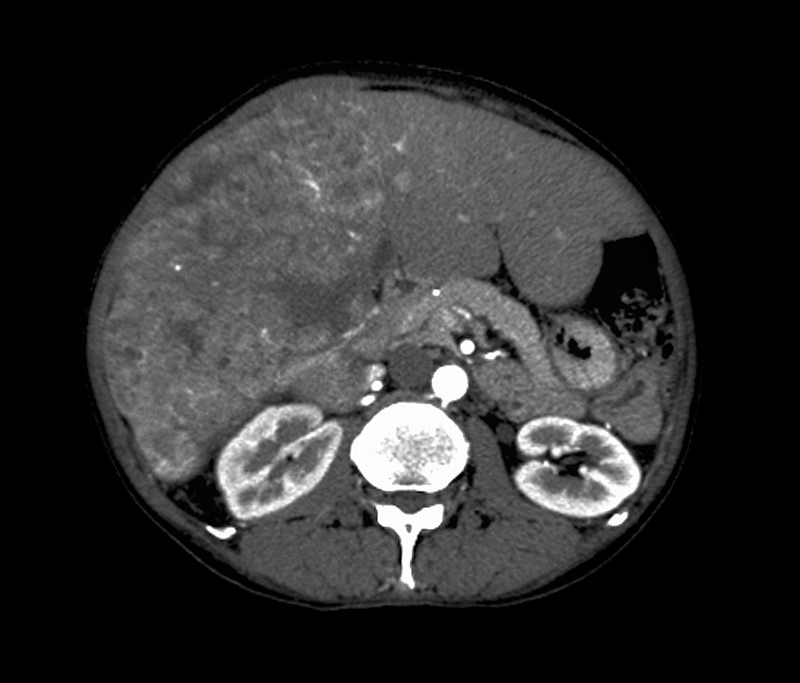

3.CT、磁共振(MRI)检查

超声发现异常后,通过这两项检查能更准确地显示肝脏病变的位置、大小、形态以及与周围组织的关系,对肝癌的诊断具有重要价值。MRI检查则对软组织的分辨力更高,对于一些CT难以确诊的病变,MRI可能会提供更准确的信息。